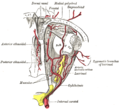

The ophthalmic artery and its branches. (optic nerve is yellow)